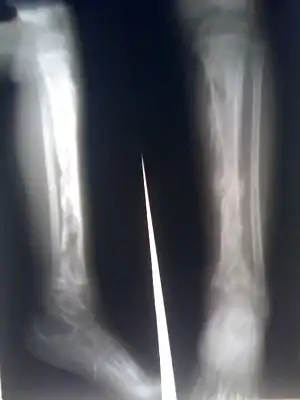

| کورک استخوان درشتنی یک نوجوان. آبسههای فراوان در استخوان به صورت روشنتر نشان داده شدهاند. | |